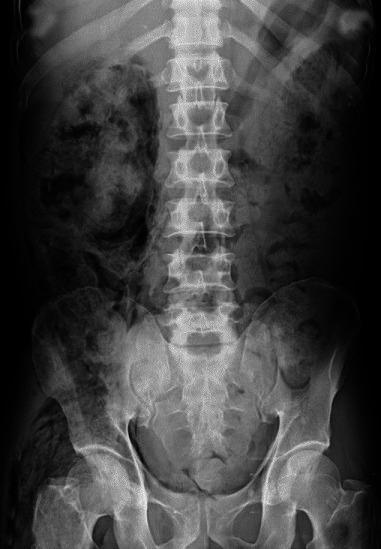

We present our experience of 22 cases of emphysematous pyelonephritis (EPN) treated from 1996 to 2012. Medical records were analyzed retrospectively for demographic profile, presence and duration of diabetes mellitus, and mode of clinical presentation. EPN was diagnosed based on demonstration of intra-renal gas by plain X-ray, ultrasound, and/or computed tomography (CT) scan. Details of medical treatment, reason for surgical intervention, and final outcome were recorded. Univariate analysis was performed to identify risk factors for mortality and P value of less than 0.05 was taken as significant. Twenty-two cases (6 males, 16 females) of EPN were diagnosed. Seven cases presented with acute pyelonephritis, seven cases with urosepsis, and the remaining eight patients with multi-organ dysfunction. CT grading of EPN was class IV in three, class III in four, class II in 14, and class I in one. All were initially managed medically with parenteral antibiotics. Ten patients needed additional surgical intervention. The overall survival rate was 86.3% (19/22). Among the risk factors analyzed higher CT grade, altered sensorium and thrombocytopenia were significantly associated with mortality. We conclude that a more conservative approach in managing EPN has become the standard of care. Patients having high CT grade of lesions (III and IV) with altered sensorium and thrombocytopenia at presentation are more likely to die due to the disease and may be better managed by an aggressive surgical plan.